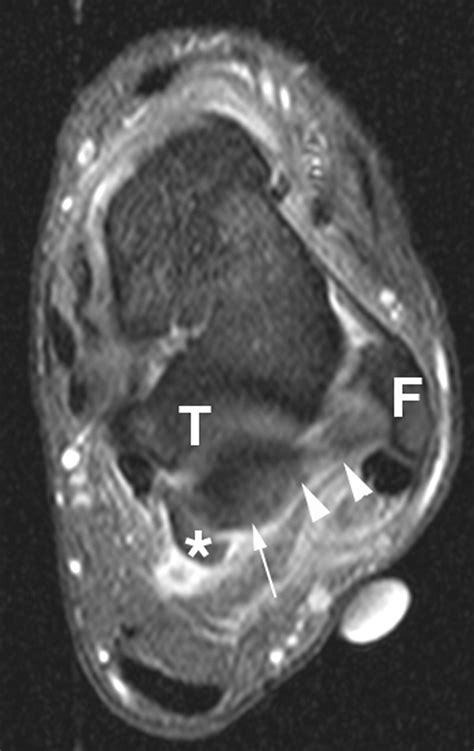

Imaging tests, such as X-rays, MRI, or CT scans, can provide detailed images of the ankle joint and surrounding structures. These tests can help identify any abnormalities, such as bone spurs, fractures, or soft tissue damage, that may be contributing to the symptoms.

• posterior ankle impingement mri